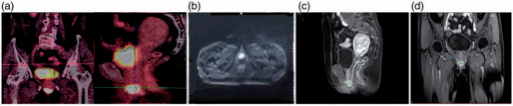

Figure 2. Images of the urethral orifice melanoma. (a) Positron emission tomography/computed tomography imaging. Before treatment, a high standardized uptake value was observed. (b) Diffusion-weighted imaging demonstrated a high-intensity lesion. (c) T1-weighted contrast-enhanced sagittal imaging also demonstrated a high-intensity lesion. (d) Coronal magnetic resonance imaging.

A woman in her early 70s was referred to our center to undergo CIRT for a urethral orifice MM. In the latter half of 2018, she had experienced discomfort and a swelling sensation of the urethral orifice while performing physical activity, and these symptoms were accompanied by urinary frequency and urgency. The symptoms gradually became aggravated during the next 3 months. Soon thereafter, a nontender, dark brown, indurated mass resembling a plum was found at the urethral orifice (Figure 1(a)). During the following 3 months, the mass progressively enlarged and the patient developed dysuria and a burning sensation during urination. At the end of 2018, cystoscopy at a local hospital showed an approximately 3-cm dark brown mass at the urethral orifice (Figure 1(b)). Pathological examination of a needle biopsy specimen showed MM, and immunohistochemical examination showed CKP (-), HMB45 (-), S-100 (-), melan-A (+), vimentin (+), CD30 (-), and Ki-67 (+70%) (Figure 1(c)). Fluorodeoxyglucose-positron emission tomography/computed tomography (CT) showed abnormally increased fluorodeoxyglucose uptake in the urethral orifice (29 × 26 × 26mm) with a maximum standardized uptake value of 48.6 (Figure 2(a)).

Magnetic resonance imaging (MRI) showed a round high-intensity lesion at the urethral orifice on T2-weighted imaging, similar to the findings on T1-weighted imaging and diffusion-weighted imaging (Figure 2(b–d)), with an apparent diffusion coefficient of 0.88×10⁻³ mm²/s and significant enhancement (Figure 2(c) and (d)). On gynecologic examination, a round mass was found at the urethral orifice at the 6-o’clock position with the patient in the lithotomy position. The lesion invaded the vaginal wall, measured approximately 2.5 × 2.4 × 2.0cm, and was dark brown and hard on palpation. It had a smooth surface and limited mobility, no tenderness, no obvious ulcer or bleeding, and no purulent secretion. The diagnosis was urethral MM cT4aN0M0 IIb (Revised American Joint Committee on Cancer 2002 tumor-node-metastasis melanoma staging system).¹¹ The patient had no cancer-related family history. She refused to undergo surgical treatment, so she was transferred to our center for CIRT. The patient was immobilized in the lithotomy position and underwent CT simulation using a four-dimensional CT system with 3-mm-thick slices. Treatment planning was performed using the ciPlan system, version 1.0 (Institute of Modern Physics, Lanzhou, China). The target area was delineated on the CT images. The gross target volume was the urethral orifice mass on CT, fused with the MRI and positron emission tomography/CT images. The clinical target volume included the gross target volume plus a 5-mm margin to encompass the surrounding tissue at risk of microscopic involvement. The planning target volume consisted of the clinical target volume plus an isotropic 3-mm margin for positioning errors during daily radiotherapy.